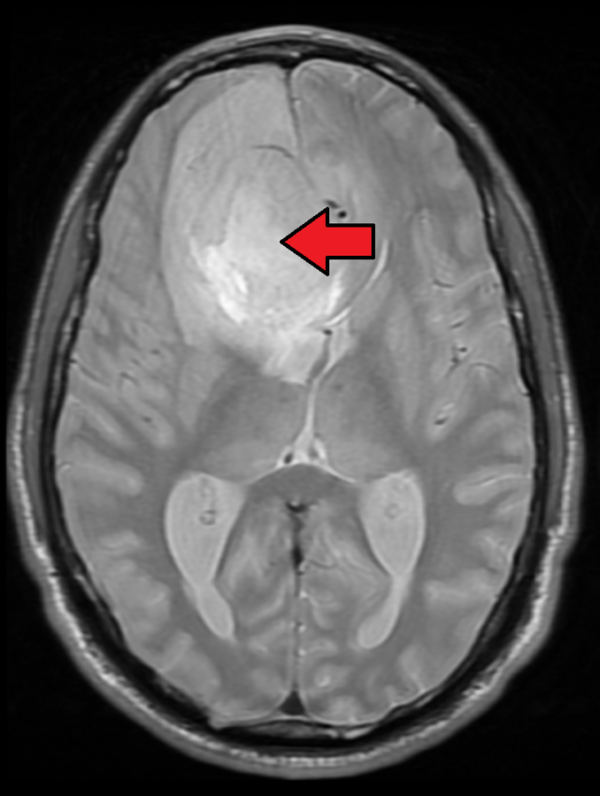

For a brain tumor to cause facial or eye twitching, it must be located in a very specific, sensitive area near the brainstem, where the cranial nerves originate.

The most common area involved is the Cerebellopontine Angle (CPA). Tumors in this area, such as acoustic neuromas (vestibular schwannomas) or meningiomas, can grow large enough to compress the facial nerve as it exits the brainstem.

If a tumor is causing facial irritation, it is usually found in the posterior fossa. This location doesn't just impact CN VII; it often causes multiple neurological symptoms simultaneously.

A specialist, usually a Neurologist, can properly diagnose the cause. Diagnosis often involves a detailed physical exam focusing on cranial nerve function and potentially imaging tests like an MRI to rule out structural issues, which would identify if a *Brain Tumor Eye Twitch* is truly the issue.